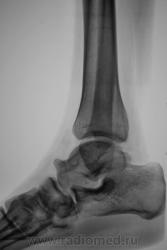

Пол пациента: Женский пол Тип патологии: Другое Область исследования: Другое Методы исследования: Rg Просто вопрос. Как можно рассматривать такую таранную кость? Гипертрофия, таран-гигант? https://radiomed.ru/sites/default/files/styles/case_slider_image/public/user/12/2.Gigant.jpg?itok=4HzRJNWV https://radiomed.ru/sites/default/files/styles/case_slider_image/public/user/12/3.Gigant..jpg?itok=HK478Gsj ID:3017 Thu, 15/04/2010 - 21:11 #1 Анатолий Владим... Offline Last seen: 7 years 11 months ago Joined: 16.10.2009 - 21:16 Posts: 1941 Вариант развития таранной кости, а насчет сапогов и венкомата не знаю... Thu, 15/04/2010 - 21:17 #2 Катенёв Валенти... Offline Last seen: 7 years 2 months ago Joined: 22.03.2008 - 22:15 Posts: 54876 Здравствуйте Анатолий Владимирович! Нет, это не военкомат. Если-бы был военкомат, то был-бы явно не годен не благодаря самой таранной кости, а той "стоялке", что по передне-верхнему краю таранной кости. Thu, 15/04/2010 - 21:23 #3 Almo Offline Last seen: 13 hours 49 min ago Joined: 28.09.2008 - 18:50 Posts: 8282 Поддерживаю пост Анатолия Владимировича-вариант развития таранной кости. Thu, 15/04/2010 - 21:46 #4 Катенёв Валенти... Offline Last seen: 7 years 2 months ago Joined: 22.03.2008 - 22:15 Posts: 54876 Как расценивать такое положение головки плечевой кости и состояние ключично-акромиального сочленения? Приложения: Thu, 15/04/2010 - 21:58 #5 Анатолий Владим... Offline Last seen: 7 years 11 months ago Joined: 16.10.2009 - 21:16 Posts: 1941 Вероятно врожденная деформация... Thu, 15/04/2010 - 21:58 #6 Катенёв Валенти... Offline Last seen: 7 years 2 months ago Joined: 22.03.2008 - 22:15 Posts: 54876 Это я решил попробовать Вашу идею, Анатолий Владимирович, "с учетом одного снимка" Thu, 15/04/2010 - 22:01 #7 Анатолий Владим... Offline Last seen: 7 years 11 months ago Joined: 16.10.2009 - 21:16 Posts: 1941 Здравствуйте Валентин Львович! Может это приживется.... Thu, 15/04/2010 - 22:13 #8 Катенёв Валенти... Offline Last seen: 7 years 2 months ago Joined: 22.03.2008 - 22:15 Posts: 54876 Будем надеяться.

Вариант развития таранной кости, а насчет сапогов и венкомата не знаю...

Нет, это не военкомат. Если-бы был военкомат, то был-бы явно не годен не благодаря самой таранной кости, а той "стоялке", что по передне-верхнему краю таранной кости.

Поддерживаю пост Анатолия Владимировича-вариант развития таранной кости.